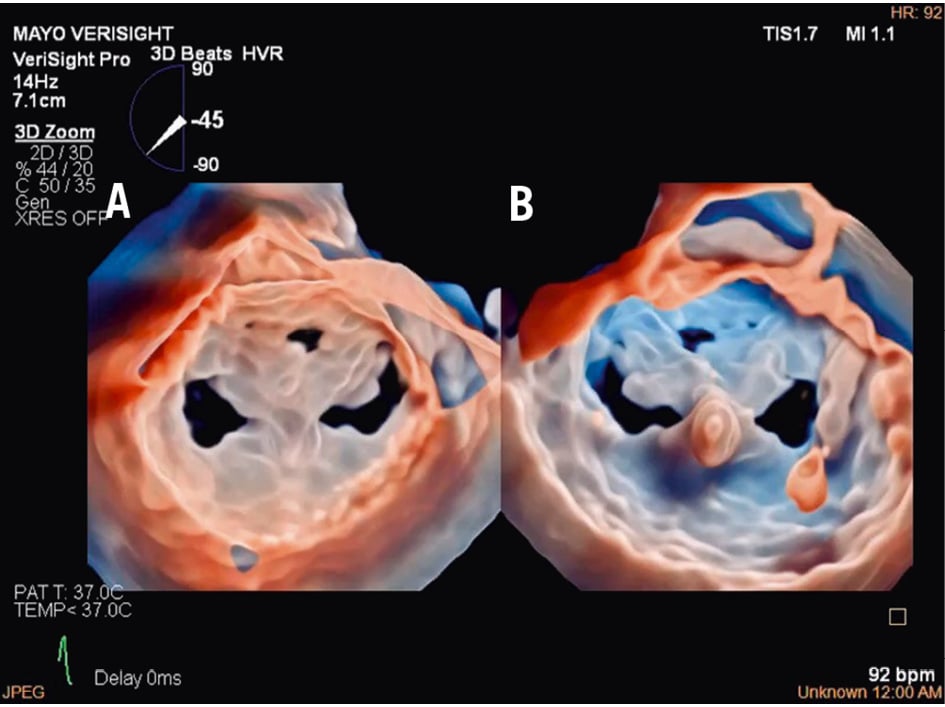

Figure 8. Three-dimensional true surgical view and left ventricular view of the mitral valve after TEER. A) 3D true surgical view; (B) left ventricular view. 3D: three-dimensional; TEER: transcatheter edge-to-edge repair